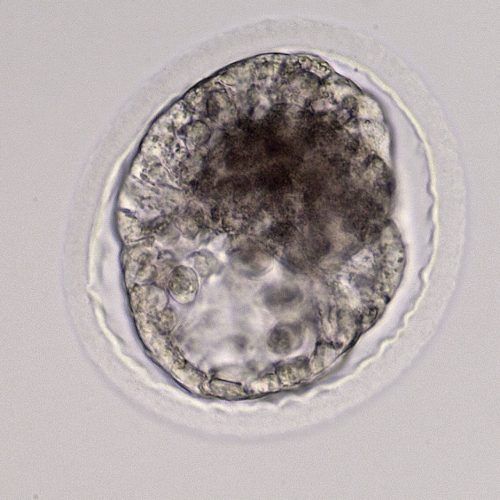

- Capsule: The embryonic capsule is unique among domestic mammals. This is a glycoprotein protective coat formed by the trophoblast layer beneath the zona pellucida. It forms only after the embryo enters the uterus, so embryos grown in a laboratory do not develop the capsule until after they are transferred. If not protected by either the zona pellucida or the embryo capsule, an embryo cannot survive in the uterus.

- Growth rate: Once the embryo becomes a blastocyst and starts expanding around day seven, the embryo will nearly double in size each day until day 12. This allows early ultrasound determination of pregnancy status, as an embryo around 300-400 microns (0.3-0.4mm) in size when recovered at day seven will grow to 3-4mm, large enough to be visualized on an ultrasound scan, by day 11.